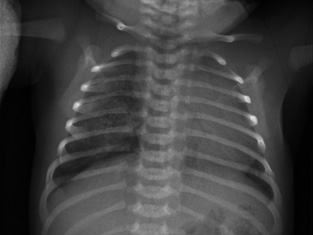

Gestante de 44 años a la que, en el control ecográfico del segundo trimestre, detectan una masa quística pulmonar de 21 x 19 x 17 mm, sin otras malformaciones asociadas. Cribado de cromosomopatías negativo y resto del embarazo sin incidencias, salvo hipotiroidismo subclínico. En controles subsiguientes persiste la masa con leve disminución de su tamaño sin asociar otros hallazgos patológicos. Nace un varón a término con llanto espontáneo, adecuado tono y coloración, con exploración física a las 8 horas de vida sin alteraciones. Ante hallazgos en ecografía prenatal, se solicita una radiografía de tórax que evidencia un aumento de densidad de morfología nodular, de unos 2 cm de diámetro, localizado en campos medios-inferiores derechos, que presenta imágenes radiolucentes milimétricas en su interior (Fig. 6). Es dado de alta sin incidencias a las 48 horas de vida. Figura 6. Radiografía del paciente en el primer día de vida. Se valora de forma presencial en consulta de neumología al mes de vida. El paciente no ha presentado infecciones respiratorias ni episodios de cianosis. Realiza tomas de manera correcta. Adecuado desarrollo ponderoestatural. Patrón respiratorio con rachas de polipnea sin tiraje. Para filiar mejor la lesión, se solicita TACAR, que se realiza a los 2 meses de vida, en el que se observa hipoatenuación e hipovascularización en lóbulo medio sin lesiones quísticas definidas. No efecto masa sobre estructuras mediastínicas ni parénquima pulmonar adyacente. Hallazgos compatibles con enfisema lobar (Fig. 7). Figura 7. TACAR del paciente a los 2 meses de vida. Controles trimestrales durante el primer año de vida. El paciente permanece asintomático. Se deriva a cardiología para descartar cardiopatía estructural asociada. A los 9 meses, radiografía de control que muestra disminución del área hiperdensa respecto al estudio previo.